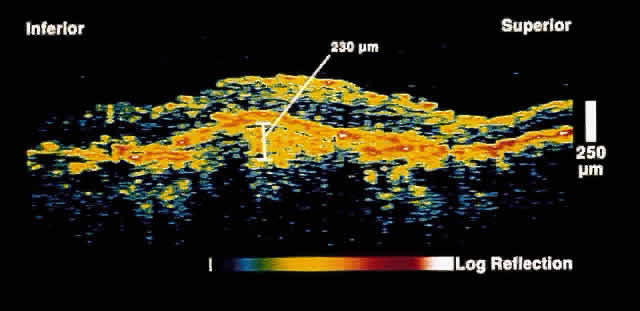

choriocapillaris/RPE layer.  Fig. 2. OCT image shows a neurosensory detachment secondary to central serous chorioretinopathy. The

difference in optical reflectivity between the posterior

boundary of the neurosensory retina and the underlying serous

fluid allows even small areas of elevation to be detected. Fig. 2. OCT image shows a neurosensory detachment secondary to central serous chorioretinopathy. The

difference in optical reflectivity between the posterior

boundary of the neurosensory retina and the underlying serous

fluid allows even small areas of elevation to be detected.